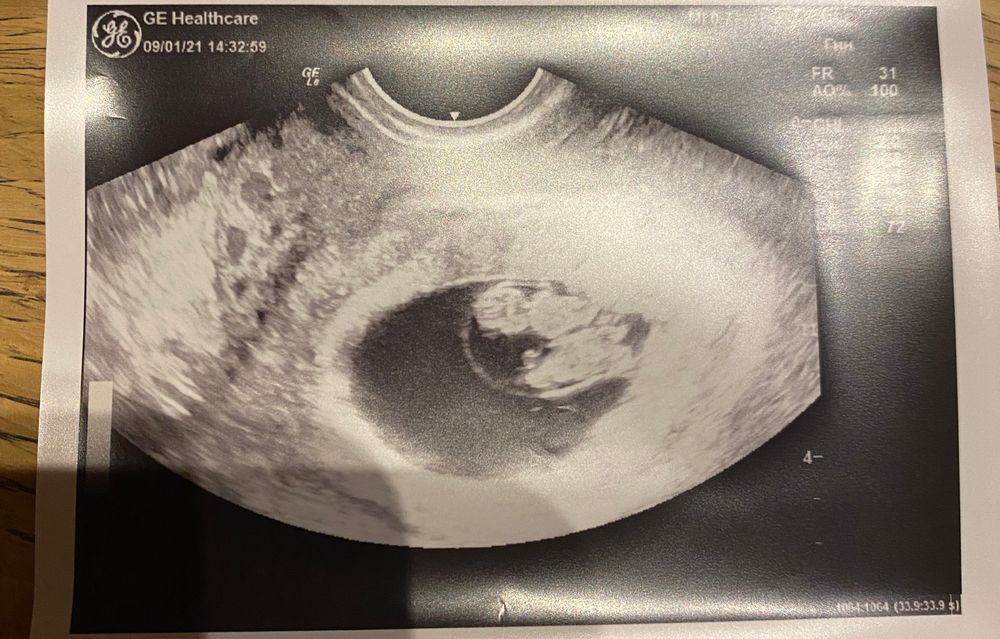

Анастасия, я сейчас добавлю своё узи, там без вариантов) они уже в обнимку лежат и амниотический мешок вокруг виден один. Вообще, по факту перегородки не бывает это просто так объясняют. Когда есть перегородка это на самом деле 2 амниотических мешка. Ну и я уже была на экспертном узи, профессор тоже сказал что когда мешок такой ровный и круглый тут практически без шансов, что она появится.

Надеюсь вы найдёте хорошего врача. Видела ваше узи, такие кошечки 🥰🥰🥰 Хорошей и лёгкой беременности вам 😻